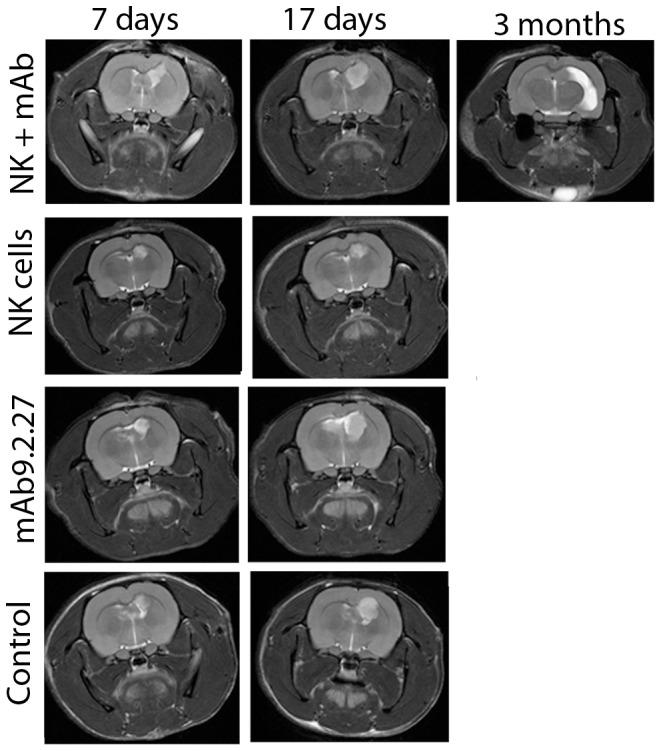

There are currently no established radiological parameters that predict response to immunotherapy. We hypothesised that multiparametric, longitudinal magnetic resonance imaging (MRI) of physiological parameters and pharmacokinetic models might detect early biological responses to immunotherapy for glioblastoma targeting NG2/CSPG4 with mAb9.2.27 combined with natural killer (NK) cells. Contrast enhanced conventional T1-weighted MRI at 7±1 and 17±2 days post-treatment failed to detect differences in tumour size between the treatment groups, whereas, follow-up scans at 3 months demonstrated diminished signal intensity and tumour volume in the surviving NK+mAb9.2.27 treated animals. Notably, interstitial volume fraction (ve), was significantly increased in the NK+mAb9.2.27 combination therapy group compared mAb9.2.27 and NK cell monotherapy groups (p = 0.002 and p = 0.017 respectively) in cohort 1 animals treated with 1 million NK cells. ve was reproducibly increased in the combination NK+mAb9.2.27 compared to NK cell monotherapy in cohort 2 treated with increased dose of 2 million NK cells (p<0.0001), indicating greater cell death induced by NK+mAb9.2.27 treatment. The interstitial volume fraction in the NK monotherapy group was significantly reduced compared to mAb9.2.27 monotherapy (p<0.0001) and untreated controls (p = 0.014) in the cohort 2 animals. NK cells in monotherapy were unable to kill the U87MG cells that highly expressed class I human leucocyte antigens, and diminished stress ligands for activating receptors. A significant association between apparent diffusion coefficient (ADC) of water and ve in combination NK+mAb9.2.27 and NK monotherapy treated tumours was evident, where increased ADC corresponded to reduced ve in both cases. Collectively, these data support histological measures at end-stage demonstrating diminished tumour cell proliferation and pronounced apoptosis in the NK+mAb9.2.27 treated tumours compared to the other groups. In conclusion, ve was the most reliable radiological parameter for detecting response to intralesional NK cellular therapy.

目前尚无既定的放射学参数可预测免疫治疗的反应。我们假设,针对胶质母细胞瘤,采用mAb9.2.27联合自然杀伤(NK)细胞靶向NG2/CSPG4,对生理参数进行多参数纵向磁共振成像(MRI)及药代动力学模型,可能会检测到免疫治疗的早期生物学反应。治疗后7±1天和17±2天的对比增强常规T1加权MRI未能检测到治疗组之间肿瘤大小的差异,而3个月时的随访扫描显示,存活的接受NK+mAb9.2.27治疗的动物信号强度和肿瘤体积减小。值得注意的是,在接受100万个NK细胞治疗的队列1动物中,NK+mAb9.2.27联合治疗组的间质容积分数(ve)与mAb9.2.27单药治疗组和NK细胞单药治疗组相比显著增加(分别为p = 0.002和p = 0.017)。在接受增加剂量200万个NK细胞治疗的队列2中,与NK细胞单药治疗相比,NK+mAb9.2.27联合治疗组的ve再次显著增加(p<0.0001),表明NK+mAb9.2.27治疗诱导了更大程度的细胞死亡。在队列2动物中,NK单药治疗组的间质容积分数与mAb9.2.27单药治疗组相比显著降低(p<0.0001),与未治疗的对照组相比也显著降低(p = 0.014)。单药治疗中的NK细胞无法杀死高表达I类人类白细胞抗原且激活受体的应激配体减少的U87MG细胞。在接受NK+mAb9.2.27联合治疗和NK单药治疗的肿瘤中,水的表观扩散系数(ADC)与ve之间存在显著关联,在这两种情况下,ADC增加均对应ve降低。总体而言,这些数据支持终末期的组织学测量结果,即与其他组相比,NK+mAb9.2.27治疗的肿瘤中肿瘤细胞增殖减少且凋亡明显。总之,ve是检测瘤内NK细胞治疗反应最可靠的放射学参数。